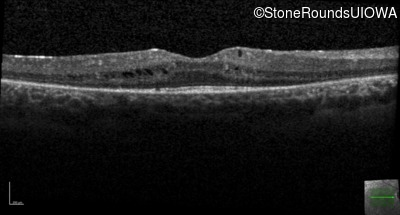

Visit at age: 21 years

Optical Coherence Tomography - Right - 20/25 -2

Exemplar / OCT Stack